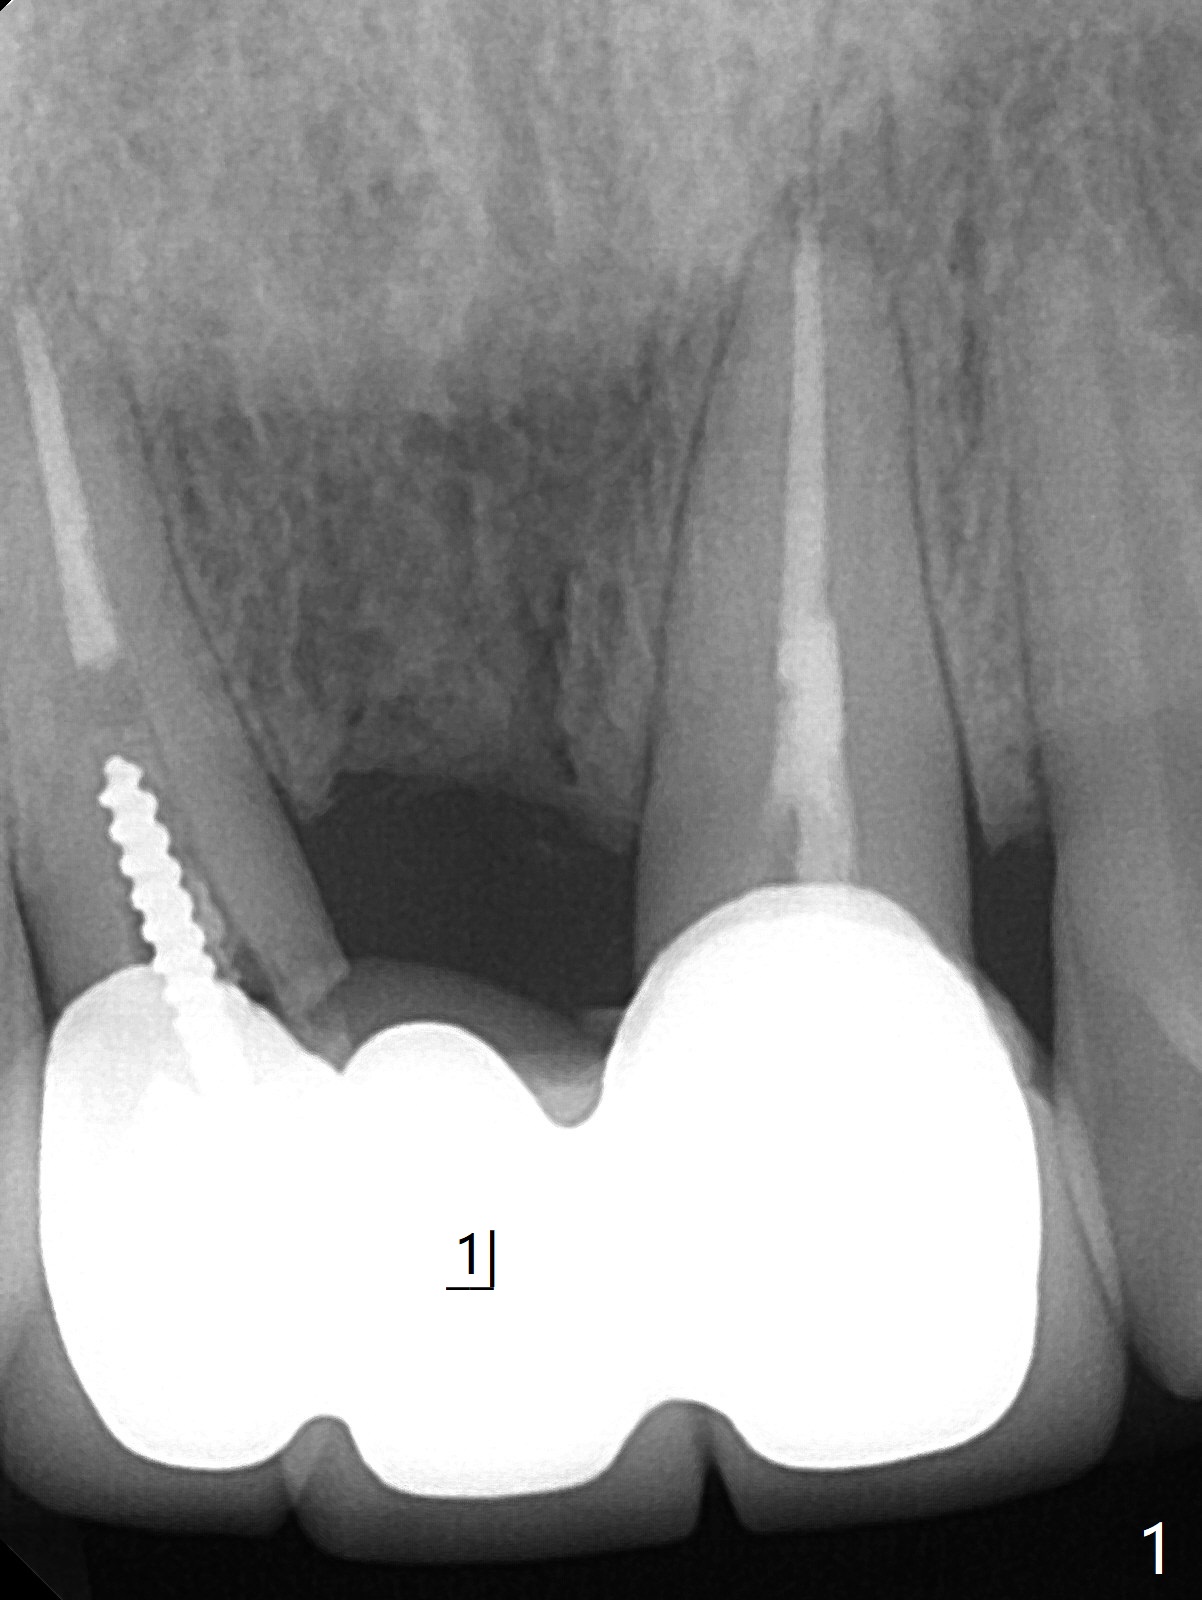

A 34-year-old woman requests fixing the failed anterior FPD (Fig.1). The edentulous alveolus looks thin; 1-piece implant may be indicated at most. A regular narrow 2-piece implant will be placed at the lateral incisor (Fig.2). CT is necessary for treatment planning. Impression has been taken for stent fabrication. 34岁女,一年半前来诊所(图一,二(侧切牙种植,做悬臂桥,暂时保留左上1牙冠)),希望修复右上门牙桥。现在终于要求立即做,基牙处牙龈红肿 (图三(今天做深洗)),牙桥颊侧移位(图四),侧切牙(7号牙)牙槽嵴也不是很宽,植入3.5毫米植体(两段式, IBS)还勉强(图五)。为了简化,避免悬臂桥,我还想在中切牙(8号牙)无牙处植入一段式2.5毫米植体(图六),适当做些牙槽嵴劈开(图六右上图:红线; from IBS cassette)。这周末徒手植入,她离开时应该有固定临时修复物。

一段式植体似乎不美观,其实它适用于近中远中空间狭窄地方,如这个病例,而两段式植体显得太粗,没有空间形成牙龈乳头,况且容易以后导致植牙周围炎。即刻临时牙冠手术第一天就起到美观作用,术后三四个月中反复调整,为永久性牙冠奠定基础。以下手术步骤就是为了这个目的。在中切牙之间切断牙桥,为右上1狭窄牙槽嵴拍摄照片(颊侧,咬合面观),切口,铬羊肠缝线牵拉,外科车针去除尖端牙槽嵴直到后者宽度达到~ 3毫米,使用1.2毫米一段式钻头,8 毫米,插入一个已经折断同样大小车针作为定位;拔除侧切牙,拍摄各式各样刮匙和肉芽组织去除器械,用1.6毫米钻头在腭侧骨板钻洞,深度9毫米,拍摄术中第一张根尖片;在中切牙处使用片状骨凿稍做骨扩张,必要时旋转式扩大器,之后完成牙槽嵴下植体放置,侧切牙牙槽窝以及中切牙术野插入无絮棉布,做必要基台制备,使用成品临时牙冠制作两个分开牙冠,确保牙龈下边缘,取出棉布,植骨,放置PRF膜,插入临时牙冠,尤其是中切牙牙冠和骨粉将改善颊侧,腭侧(与图四箭头对比)饱满度,最后缝合,调整咬合。7,8号牙骨质密度分别为700和 500单位(图七,八)。